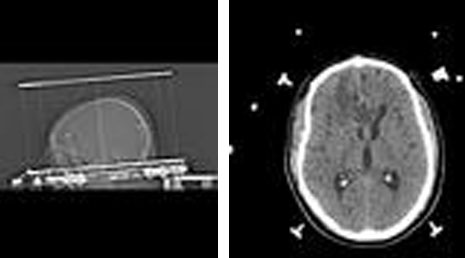

25. Cranial gunshot.